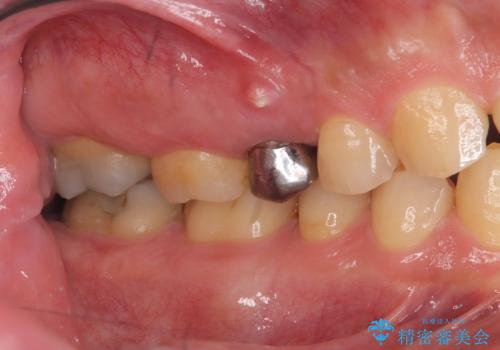

- 「歯茎にニキビみたいのが出来て歯が揺れている」を主訴に来院された患者様です。

右上5番が根尖性歯周炎と歯周病が同時に併発しており、骨が大きく溶け、歯の動揺も著しかったため保存困難と判断をし抜歯してインプラントで治療を行いました。

右上4番は虫歯になっていたので、虫歯を除去後、セラッミクインレーで治療を行いました。